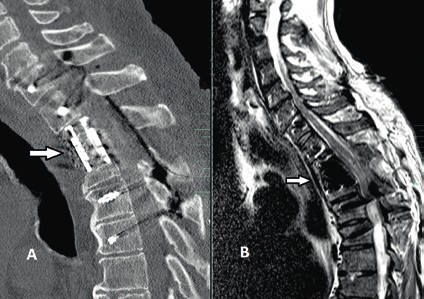

Prinzipiell richtet sich die Entscheidung, welche operative Versorgung durchgeführt wird, nach Ausmaß und Art der Verletzung. Für die Stabilisierung der dorsalen Säule reicht im Falle einer stabilen ventralen Säule die dorsale Instrumentierung aus. Hier gewährleisten dorsale Pedikelschrauben, die mit einem Stab verbunden sind, eine gute Wiederherstellung der Stabilität (Abb. 2). Im Falle einer instabilen ventralen Säule ist hingegen eine Implantation von Wirbelkörperersatz und eine dorsoventrale Segmentversteifung indiziert (Abb. 3). Die entwickelten minimalinvasiven Techniken – zum Beispiel die transkutane Pedikelschraubenimplantation oder der Wirbelkörperersatz durch endoskopische Thorakotomie – haben dazu geführt, dass das Wundgebiet und die operationsbedingte Gewebeschädigung reduziert werden und somit eine Belastungsreduktion für den Körper erzielt wird. Dieser Aspekt ist insbesondere bei älteren Patienten mit multiplen Begleiterkrankungen von Vorteil. Im Falle einer osteoporotischen Wirbelsäule werden die implantierten Pedikelschrauben zementiert (Abb. 4). Auch hier erlaubt die Entwicklung fenestrierter Schrauben eine optimale Möglichkeit der Zementapplikation.

Weitere neurochirurgische Aspekte der operativen Behandlung traumatischer Querschnittläsionen und deren Spätfolgen sind die operative Therapie der posttraumatischen Syringomyelie und die der spastischen Lähmung. Obwohl mehr als die Hälfte aller Patienten mit Querschnittläsionen an der Verletzungsstelle eine Zyste – meistens ohne Dynamik oder Wachstumstendenz – im Rückenmark entwickeln, entsteht eine symptomatische posttraumatische Syringomyelie bei ca. 4 % der Patienten innerhalb von 6 Monaten bis zu mehreren Jahren. Die Entstehungsmechanismen der posttraumatischen Syringomyelie sind nicht gänzlich geklärt; jedoch wird ein multifaktorielles Geschehen postuliert, in dem residuelle Kyphosen der Wirbelsäule, Einengungen des Spinalkanals, intramedulläre Hämatome, vaskuläre Dysregulation und gestörte Liquor-Dynamik miteinander zusammenhängende Rollen spielen. Bei symptomatischer Syringomyelie und progredienter neurologischer Befundverschlechterung ist eine operative Therapie angezeigt 16 17. Die operative Therapie der Syringomyelie zielt in erster Linie auf die Beseitigung der Ursache – falls identifizierbar – ab, um ein Fortschreiten der Erkrankung zu verhindern; dabei ist eine genaue Diagnostik mit vollständiger Darstellung des kranialen und kaudalen Endes der Syrinx obligat. So kommen im Falle von residuellen Kyphosen und Einengungen des Spinalkanals dekompressive und/oder stabilisierende Verfahren mit oder ohne Duraerweiterungsplastik – wie oben beschrieben – zur Anwendung.